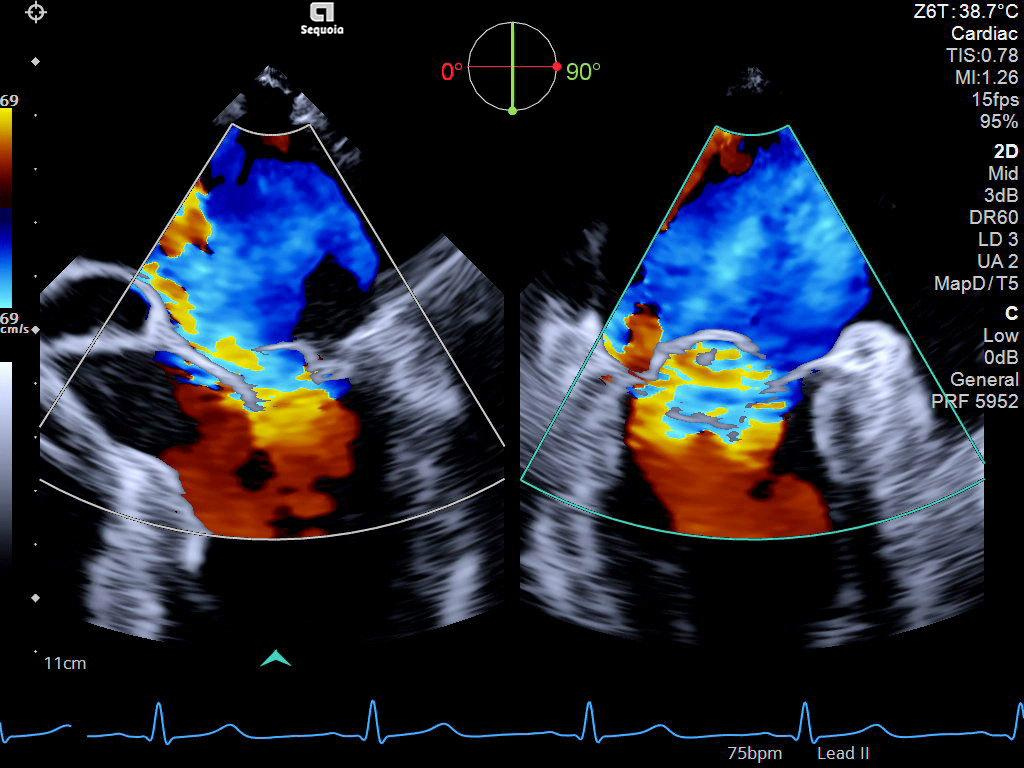

The ACUSON Sequoia is an advanced diagnostic tool that integrates cutting-edge technology and AI-powered applications to streamline diagnostic processes. This system is designed to cater to patient-specific needs, ensuring accuracy and efficiency in various clinical settings such as Radiology, OB/GYN, Shared Service and beyond.

The latest updates on ACUSON Sequoia use the power of groundbreaking AI for abdominal cases, includes advanced breast visualization to deliver new levels of image quality confidence, and tackles the toughest challenges in musculoskeletal imaging, all while saving your team from needless strain and pain.

ACUSON Sequoia’s new advanced features are designed to improve diagnostic confidence and workflow across a wide range of clinical settings.

Boost your clinical confidence with a system designed to enhance your expertise. The ACUSON Sequoia gives you the power to know more by maximizing the sensitivity and depth of your scans, while reducing variability across patients, systems and users.

ACUSON Sequoia’s InFocus imaging architecture eliminates the need for conventional focal zones to create a fully focused image faster than conventional systems. Our InFocus technology applies to all imaging transducers and exam types giving you consistent imaging across clinical segments. Some of the benefits are:

A clearer, deeper perspective with optimal acoustics for each clinical use case. Expand your assessment with advanced tools that take ultrasound beyond its traditional role.

- 4D HeartAI utilizes proprietary AI to process complex cardiac data, 4D analysis, and imaging for TTE and TEE for timely and accurate decision making.

- AI Assist alleviates time consuming echo calculations and standardize exams across users.